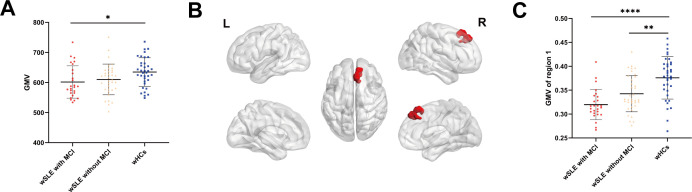

Results: In comparison to wSLE patients without MCI (n=36), wSLE with MCI (n=26) demonstrated a significant decrease in FD of the left lateral orbitofrontal gyrus. When compared with the wHC group (n=36), both wSLE patients with MCI and wSLE without MCI group exhibited a reduction in GMV in the medial of right superior frontal gyrus, a thinning of CT in the left paracentral and postcentral gyrus as well as in the right pars triangularis gyrus and superior frontal gyrus. Within the wSLE group, Mini-Mental State Examination scores were positively correlated with GMV in the middle of right superior frontal gyrus and with the FD of the left lateral orbitofrontal gyrus.